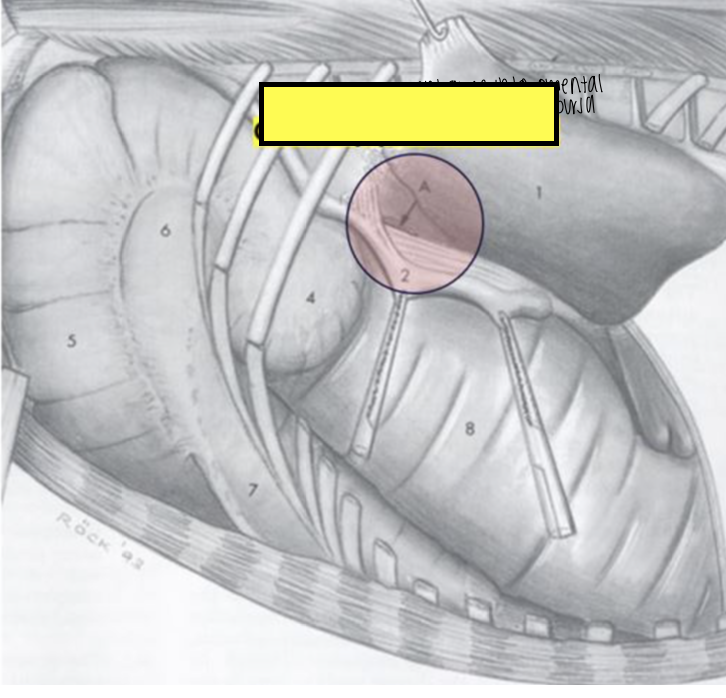

what is 5?

right lobe of equine liver

what is 4?

quadrate lobe of equine liver

what is 2 and 3?

left medial lobe of equine liver

what is 1?

left lateral lobe of equine liver

what are the lobes of the equine liver?

left lobe

quadrate lobe

right lobe

caudate lobe

what is absent in the equine liver?

no papillary process

what ligament is strong and well formed in the equine liver?

round (teres) ligament

what lobe of the liver in equine atrophies with age and why?

right lobe due to pressure from right dorsal colon

what is the location of the cranial part of the equine liver?

lower part of the 6th or 7th rib

what is the location of the caudal part of the equine liver?

16th and 17th ribs ventral to the right kidney

what is the location of the most ventral part of the equine liver?

does not reach abdominal floor; at level of 7th or 8th rib

what does the red circle indicate?

gastroepiploic foramen